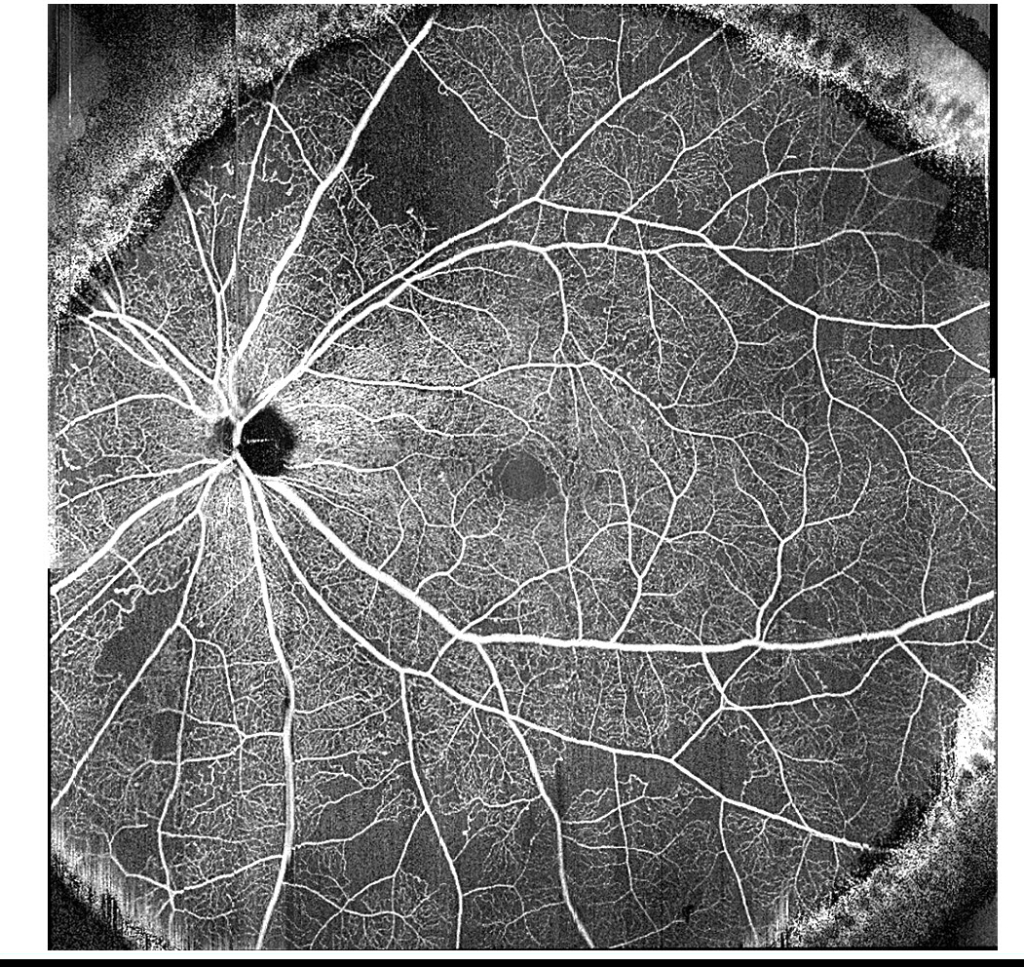

糖尿病網膜症 Diabetic Retinopathy

53歳男性左眼視力:(1.2)糖尿歴20年以上だが、血糖コントロール良好。一般的に血糖コントロール不良時には、検眼鏡的に網膜症の活動指標になる出血や軟性白斑が確認しやすい。一方で本症例のように一見サイレントで非活動性のように見えてしまうケースが少... -